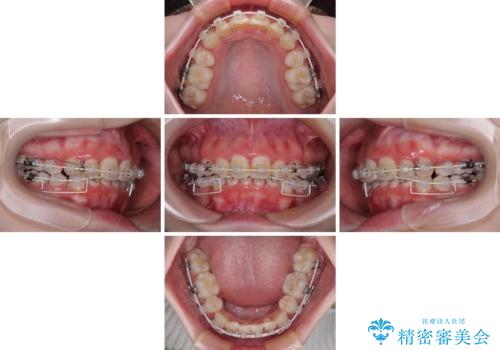

- 矯正装置

- 審美装置

- 治療期間

- 2年2ヶ月

下顎前歯が隠れるほどのディープバイトであり、それによる顎の負担も大きかったため、ディープバイトもしっかりと改善できるよう、表側のワイヤー装置にて矯正治療を行うこととしました。

ディープバイトは、治療を行っていた我々も驚くほど、短期間で劇的に改善することができました。